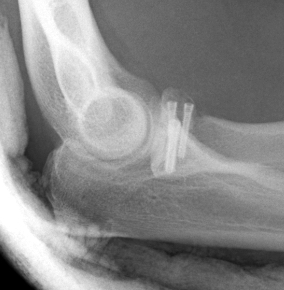

Radial head replacement with lag screw fixation of Type II coronoid

Radial head replacement with lasso fixation of small coronoid fragment